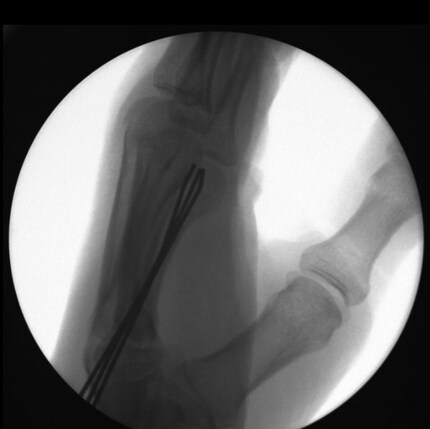

Mein linker Arm ist ein lebloses Stück Fleisch. Die Operation hat unterdessen begonnen. Der Chirurg schneidet und zieht die Drähte in die Hand. Ich fühle zwar absolut keinen Schmerz, aber es ruckelt in der Schulter. Zwischendurch hämmert er. Es macht mehrmals Klack Klack Klack. Und ich höre auch, wie der Chirurg die Drähte mit der Zange abkneift. Der Arm ist wie gesagt im Tiefschlaf und doch «spüre» ich, dass etwas in meinen Körper eindringt, was da nichts zu suchen hat. Es ist ein bisschen gruselig. Ich kann es nicht besser beschreiben.

«Alles gut?», will ich vom Chirurgen wissen. Soweit sei alles gut, meint dieser. Daumen hoch. Es seien einzig drei statt der ursprünglich geplanten zwei Kirschner-Drähte «verbaut». Naja, mehr ist immer besser. Der Chirurg kann sich ein Schmunzeln auf meine Bemerkung nicht verkneifen und meint nur: «In diesem Fall wäre weniger tatsächlich mehr».